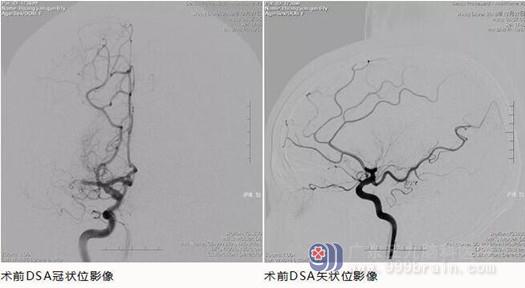

到达医院后,检查头颅CT影像,发现在右侧大脑中动脉处存在高密度影,考虑右侧大脑中动脉M1段出现栓塞。从晚上八点开始发病,到考虑是脑栓塞已经过了两个小时了。

从发病到现在已经过了八个多小时,而且已经在外院做了溶栓的处理,此时采取静脉溶栓的治疗方案已经不适用,在这种情况下如果还想要进行积极的治疗,让王阿姨有恢复的可能,就得通过机械取栓,直接将栓子从血管中取出。

好在我院自2016起开展脑梗塞绿色通道以来,已经形成一套完整的流程,可在短时间评估后迅速为患者启动溶栓取栓治疗。虽然一般基层医院对错过溶栓治疗窗或者溶栓治疗效果不显著的患者已经无计可施,但我院还可行机械取栓术进一步治疗。

在神经内一科、介入室等科室的协力合作下,最终成功的将王阿姨脑血管中的血栓取出,恢复了脑部血供。当然,王阿姨发病的症状较重,而且从发病到取出栓子之间的时间间隔也较长,所以刚开始还要在监护室观察,但是随着王阿姨病情的稳定,几天之后就已经转入到普通病房中休养。